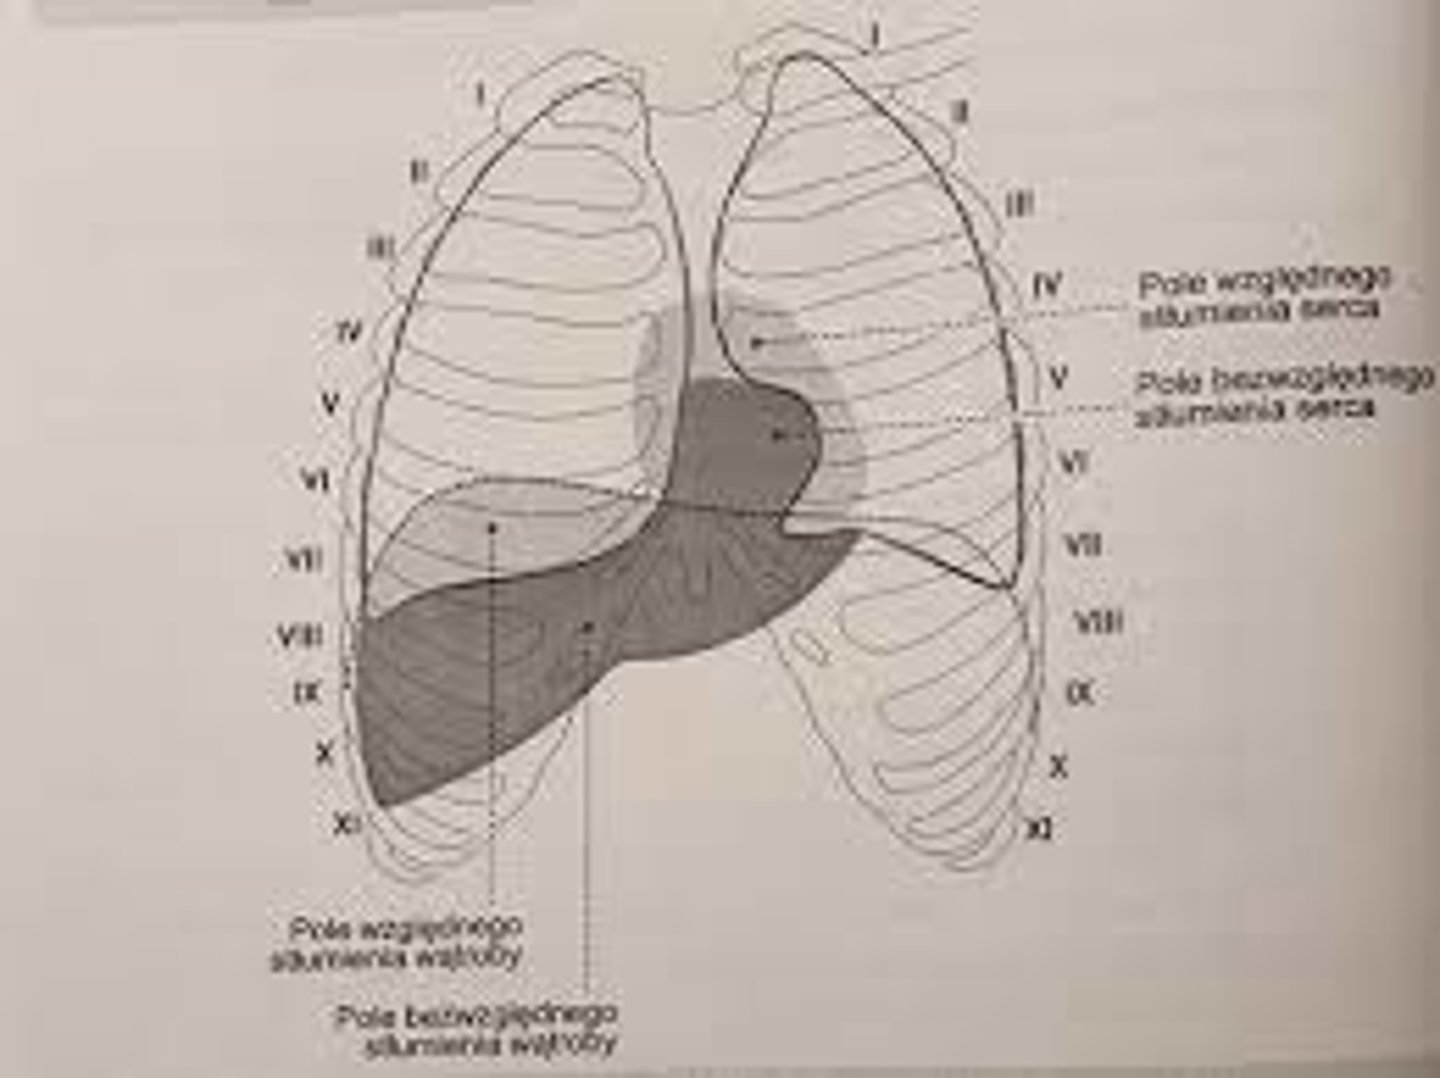

Jakie cechy można określić na podstawie opukiwania?

wielkość i kształt serca

Co wyróżnia się na podstawie różnic odgłosu opukowego?

stłumienie bezwzględne i względne

Co obejmuje pole bezwzględnego stłumienia?

u góry 4. przestrzeń międzyżebrową

od prawej brzeg przedni płuca prawego

od lewej wcięcie sercowe płuca lewego

od dołu nie da się określić granicy

Co obejmuje pole stłumienia względnego?

odpowiada obrysowi serca

górna granica: ku tyłowi od mostka na wysokości górnego brzegu żebra III

lewa granica: od górnego brzegu III żebra do miejsca uderzenia koniuszkowego w 5. przestrzeni międzyżebrowej

prawa granica: równolegle do prawego brzegu mostka

dolna granica: przechodzi w stłumienie wątroby -> brak stłumienia względnego

Jak biegnie lewy obrys serca?

od górnego brzegu III żebra do miejsca uderzenia koniuszkowego w 5. przestrzeni międzyżebrowej

Jak biegnie prawy obrys serca?

równolegle do prawego brzegu mostka, przekracza go na szerokość palca

Na jakiej wysokości znajduje się łuk aorty?

2. żebra lewego

Na jakiej wysokości znajduje się łuk pnia płucnego?

2. międzyżebrza lewego

Na jakiej wysokości znajduje się punkt przedsionkowy lewy?

3. żebra lewego

Na jakiej wysokości znajduje się łuk przedsionka lewego?

3. międzyżebrza lewego

Na jakiej wysokości znajduje się punkt lewy podstawy komór?

3. międzyżebrza lewego

Na jakiej wysokości znajduje się łuk komory lewej?

4. międzyżebrza lewego

Na jakiej wysokości znajduje się punkt koniuszka serca?

5. międzyżebrza lewego

Na jakiej wysokości znajduje się dolny obrys serca?

5. międzyżebrzy

Na jakiej wysokości znajduje się punkt prawy podstawy komór?

5. międzyżebrza prawego

Na jakiej wysokości znajduje się łuk przedsionka prawego?

4. międzyżebrza prawego

Na jakiej wysokości znajduje się punkt przedsionkowy prawy?

3. międzyżebrza prawego

Na jakiej wysokości znajduje się łuk żyły głównej górnej?

3. żebra prawego